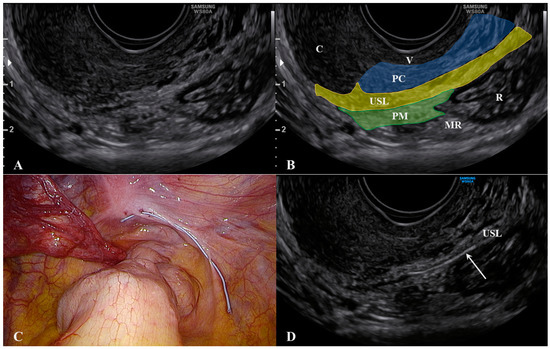

The cervix should appear on one side of the image to ensure that the edge of the ligament that is closest to the cervix can be assessed. The first important consideration during ultrasound of the USL is to not push the probe upwards while it is correctly placed. This method allows for clear visualization of not only the USL, but also the parametrium (distal to the probe) and, most importantly, the paracervix (proximal to the probe). As shown in Figure 2, we placed a 5 Ti-CronTM polyester suture (a heavy braided suture for orthopedics, diameter 0.7 mm) along a physiological USL during surgery to confirm the ultrasound visualization of the ligament. In this way, we could simultaneously visualize the vaginal wall, the paracervical tissue, the USL, and the parametrium. All structures could be visualized from the probe to more distant regions (Supplementary Materials Video S1).

Figure 2. Ultrasound visualization of the uterosacral ligament, paracervix, and parametrium. Figure (A) shows the normal appearance and explanations are reported in figure (B). A polyester suture was placed on a physiological USL during laparoscopy (figure (C) and identified via ultrasound (arrow) in figure (D). Abbreviations: C, cervix; MR, mesorectum; PC, paracervix; PM, parametrium; R, rectum; USL, uterosacral ligament; V, vagina wall.